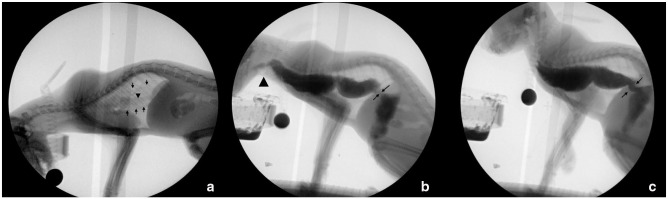

病例总结:猫食道肥大(ME)是一种罕见的食道运动障碍,会导致猫的反流、体重减轻,有时甚至死亡。它已被确定为继发于神经和神经肌肉疾病、食道机械性梗阻(如血管环异常、食道狭窄)和上气道梗阻等;当找不到病因时,被认为是特发性的。视频透视吞咽研究(VFSSs),特别是使用不受约束的自由喂养方案,尚未充分用于对反流猫的综合评估,包括确定ME的病因。在本病例报告中,一只3个月大的雄性完整家养短毛猫,自断奶以来有反流史,影像学证据显示为ME,其VFSS特征与食管下括约肌(LES)功能性梗阻相一致,符合LES贲门贲门样综合征。用药西地那非未能改善临床症状,采用Heller肌切开术和Dor底襞术矫正LES贲门失弛缓症的手术治疗被拒绝。由于护理人员对持续反流的同情疲劳,选择了安乐死。相关性和新信息:视频透视记录的LES功能性梗阻(即LES贲门亚样综合征)可以识别猫ME的新病因。建议使用自由喂养不受约束的VFSS方案,对吞咽障碍进行生理评估,且不存在比在家进食和饮水更高的误吸风险。对LES贲门弛缓样综合征的认识可能会导致针对功能性阻塞的定向治疗的进一步研究,正如已经在人类和狗身上进行的那样。

Case summary: Feline megaesophagus (ME) is a rare failure of esophageal motility leading to regurgitation, weight loss and sometimes death in cats. It has been identified secondarily to neurologic and neuromuscular disorders, mechanical obstruction of the esophagus (eg, vascular ring anomalies, esophageal stricture) and upper airway obstruction among others; when no cause is found, it is considered idiopathic. Videofluoroscopic swallow studies (VFSSs), especially using an unrestrained free-feeding protocol, are underutilized for comprehensive evaluation of cats with regurgitation, including identifying the etiology of ME. In this case report, a 3-month-old male intact domestic shorthair cat with a history of regurgitation since weaning and radiographic evidence of ME had VFSS features compatible with a functional obstruction of the lower esophageal sphincter (LES) consistent with LES achalasia-like syndrome. Medical management with sildenafil failed to improve clinical signs, and surgical correction of LES achalasia using a Heller myotomy and Dor fundoplication was declined. As a result of caregiver compassion fatigue from persistent regurgitation, euthanasia was elected.

Relevance and novel information: Videofluoroscopic documentation of functional obstruction of the LES (ie, LES achalasia-like syndrome) can identify a novel etiology of feline ME. Free-feeding unrestrained VFSS protocols are recommended to allow physiologic assessment of swallowing disorders with no higher risk of aspiration than eating and drinking at home. Recognition of LES achalasia-like syndrome may lead to further study of directed treatments targeting the functional obstruction as has been carried out in humans and dogs.